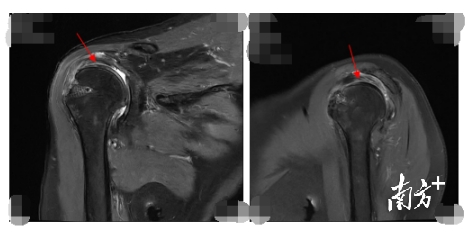

△图中箭头所示术后半年上关节囊重建后移植物位置良好。

手术中,何河北副主任医师使用患者大腿的阔筋膜,在关节镜下,只开4个微创小切口,在关节盂侧使用2枚带线锚钉,在肱骨头侧使用3枚带线锚钉,将阔筋膜按肩袖大小重建起来。